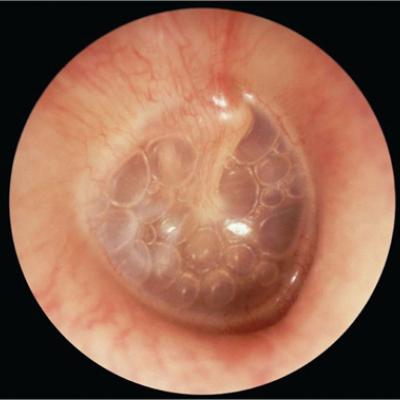

- Observe the tympanic membrane (TM) for redness, inflammation, leaking of fluid, bulging, myringotomy tubes, or perforations. Typically the TM should be mostly flat, gray, kind of shiny, and somewhat translucent.

- Fluid in ear: this can be difficult to see at times but you might see a few bubbles behind the TM. Sometimes if there is a lot of fluid it can cause the TM to bulge out and you can see the line of fluid behind the TM. Fluid in the ear can be caused by allergies, a cold virus or an ear infection.